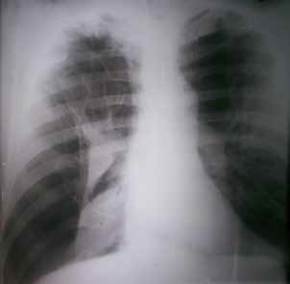

En la radiografía postero-anterior inicial de tórax en bipedestación se encontró colapso del pulmón derecho con múltiples bullas enfisematosas en ambos campos pulmonares (figura 1). El lóbulo superior derecho presentaba signos de atrapamiento de aire por la existencia de enfisema pulmonar, con aumento de su radiotransparencia. Las costillas se encontraban ‘horizontalizadas’ y había ensanchamiento de los espacios intercostales, y descenso y aplanamiento del diafragma.